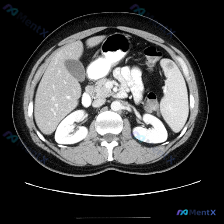

- 检查手段:腹部CT横断面,软组织窗

- 增强状态:根据血管及实质强化,考虑为静脉期/平衡期

- 扫描层面:上腹部,包含肝、胆、脾、胰(部分)、双肾及腹主动脉等

- 脾脏:形态、大小正常,实质密度均匀,强化一致,脾周脂肪间隙清晰

- 其余实质脏器:肝、胆、胰、双肾均未见明确占位、扩张或渗出

- 血管与腹膜后:腹主动脉、下腔静脉走行正常,腹膜后未见明确肿大淋巴结

- 其他:胃肠道、可见骨质均无明显异常

总结一句话:这张图里,没看到任何脾脏病变,也没看到其余腹部的明确病理征象。